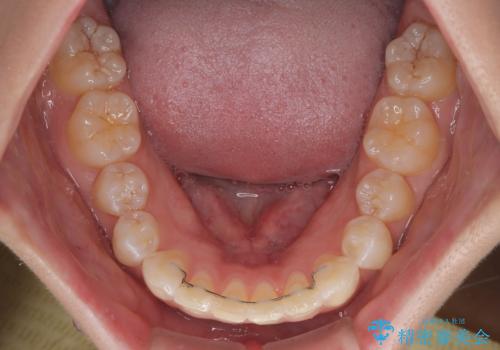

なかなか舌の突出癖が改善できず、上下前歯が非接触となる期間が長く続きました。

アンカースクリューの活用と、舌のトレーニングを何度も指導し、出っ歯になることなく無事に治療を終えることができました。